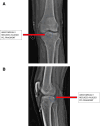

This study describes a method of fixing posterior cruciate ligament (PCL) avulsion fractures called the arthroscopic crisscross technique. PCL avulsion fracture is a rare injury that generally occurs in young patients. A displaced avulsion fracture at the tibial attachment of the PCL is an indication for surgical reduction and internal fixation given that nonunion, posterior instability, and early degenerative changes of the knee are common consequences of conservative treatment. This study describes all-arthroscopic fixation of the PCL avulsion injury using 2 No. 2 FiberTape sutures (nonabsorbable polyblend; Arthrex) via the arthroscopic crisscross technique. The No. 2 FiberTapes crisscross each other over the avulsed fragment. Through tensioning of both No. 2 FiberTapes, they are fixed anteriorly using a suture button. This technique can be considered a safe and effective method using minimal resources for the fixation of the avulsed PCL from its tibial footprint.